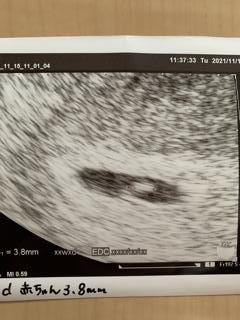

赤ちゃんは3.8㍉、心拍ピコピコもモニターで確認できました♡